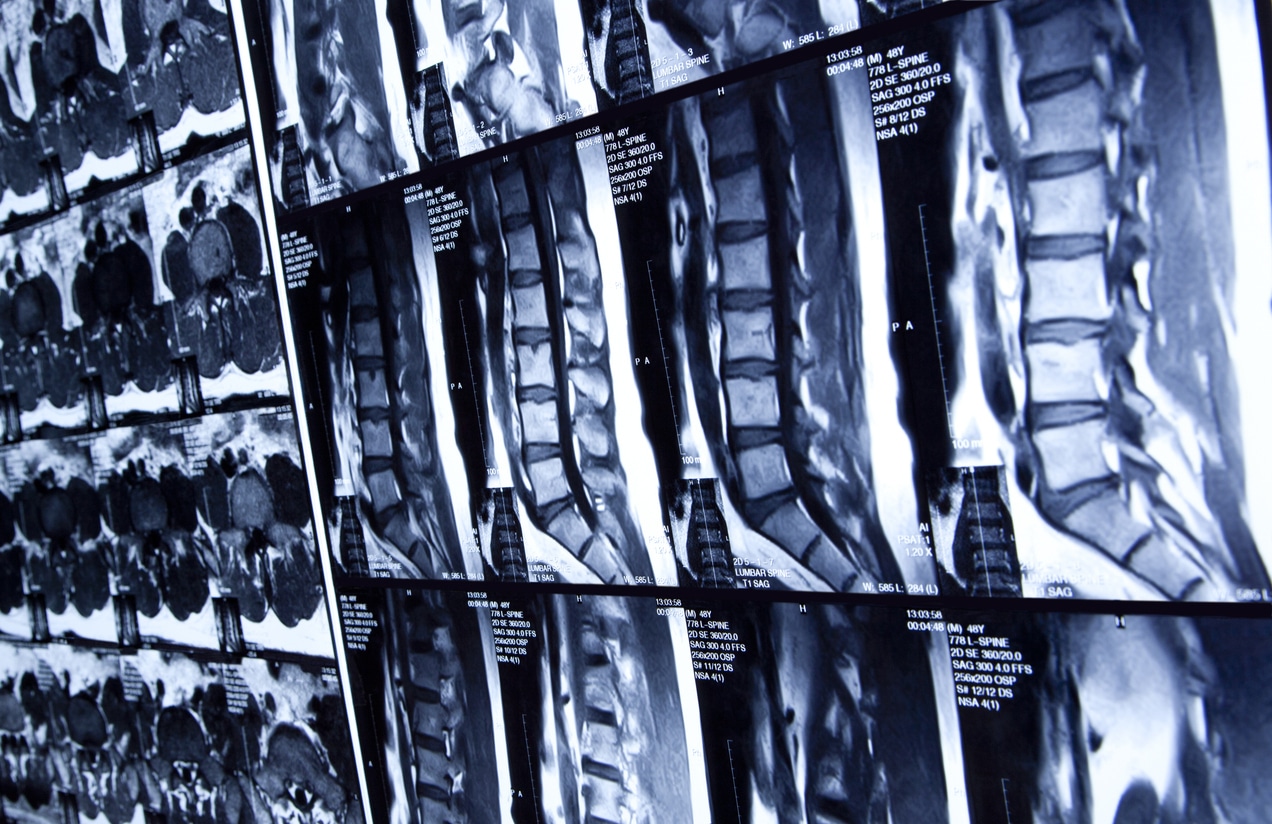

Multiple MRI scans of human spine

Though spinal deformity is common among certain populations, there are a variety of spine conditions that may cause similar symptoms. An accurate diagnosis is necessary for effective treatment. At NU-Spine, diagnoses are performed by Dr. Branko Skovrlj. The process begins with a physical exam to test your mobility and check for areas of sensitivity. He may also request imaging tests, such as:

• X-Ray

• CT scans

• MRI